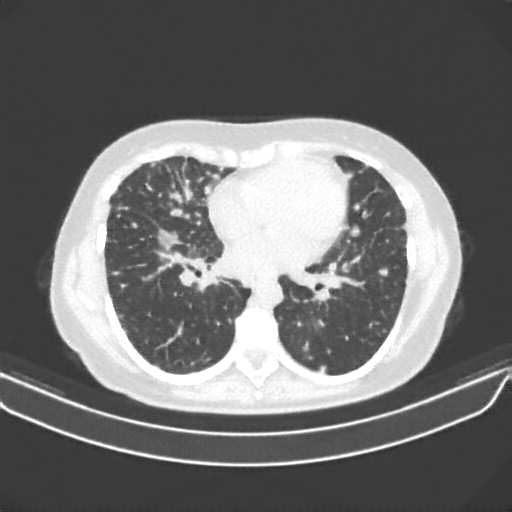

Generated VENOUS CT scan (A→B translation)

No window - Raw intensity values

Lung window (WL -600, WW 1500 β†’ Low βˆ’1350, High +150)

Mediastinum window (WL 40, WW 400 β†’ Low βˆ’160, High +240)